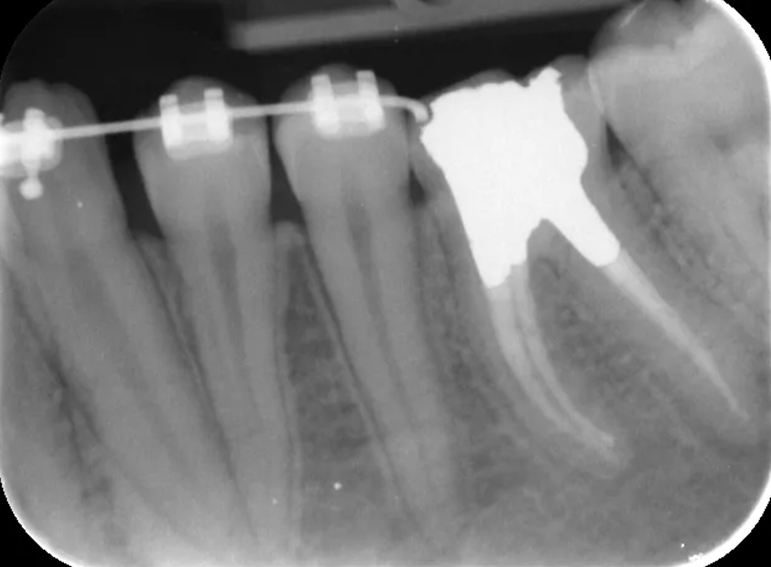

Root filling revision of a lower molar.